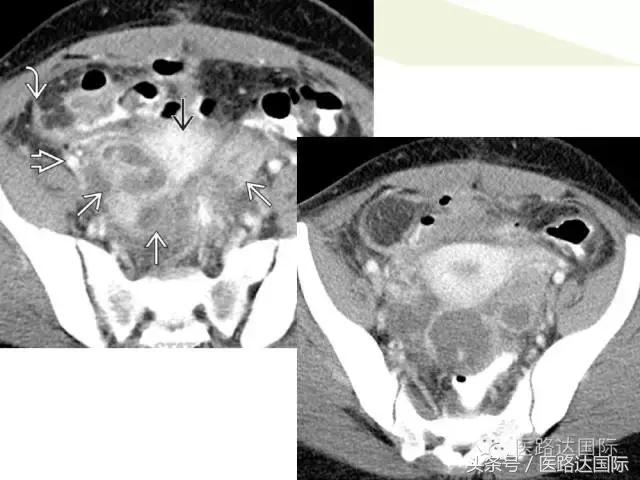

首都医科大学附属北京妇产医院梁宇霆教授从流行病学、临床特点、实验室检查、病理改变、影像学特点及治疗与预后六个方面向我们详细地介绍了女性生殖系统结核;并且着重介绍了子宫输卵管造影(HSG)的作用。在最后,梁教授还向大家介绍了如何鉴别诊断女性生殖系统结核、盆腔炎性病变和卵巢癌。

女性生殖系统结核的影像诊断及鉴别